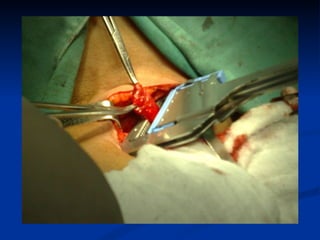

El documento habla sobre la anatomía y trastornos del esófago. Menciona las condiciones como el esófago de Barrett, el divertículo de Zencker, la acalasia y el cáncer de esófago, describiendo sus síntomas y tratamientos. Explica que el esófago de Barrett aumenta el riesgo de cáncer esofágico y que la acalasia se caracteriza por la hipertrofia del esfínter esofágico inferior y la ausencia de peristaltismo. También cubre factores de riesgo